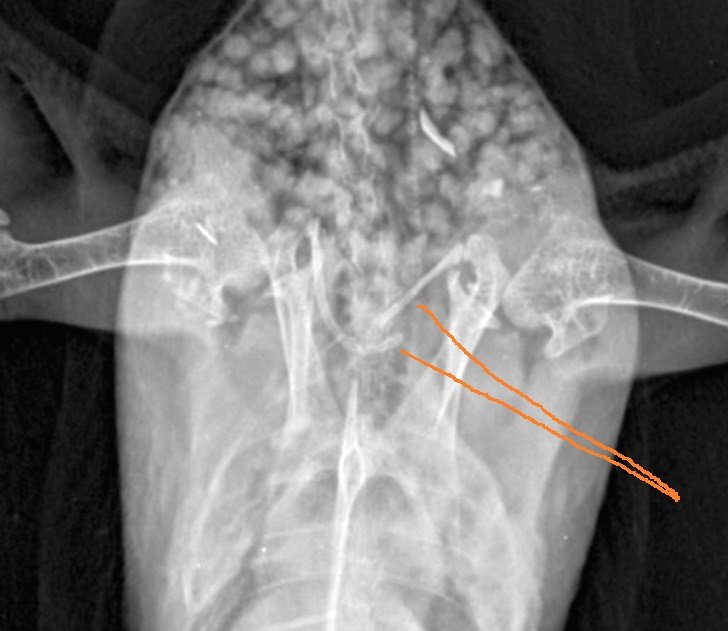

Zosia Опубликовано 15 апреля, 2023 #8 Опубликовано 15 апреля, 2023 боковая проекция тут не нужна... вот ниже немного поиграла со снимком и указываю зону перелома. Я бы даже сказала отлома правой ветки ключицы ("воронья кость"). Она просто отчленена. Смещение большое, не срастется Полноценно летать не сможет . Я бы сейчас состригла оперение с обоих крыльев, все большие перья. И на 5 недель- переноска или большая коробка. Мелоксикам на 2-3 недели. Остеогенон на месяц. Любое движение крыльев вызывает шевеление отломков, которые травмируют окружающие ткани. Надо надеяться хотя бы на из фиксацию к плечевым костям, что очень сомнительно... 1